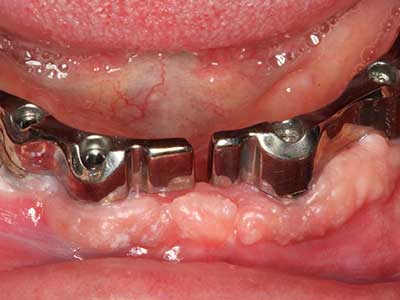

Indication: Preparation near nerves

As noted above, indications for piezo surgery can also be found in the field of conservative dental surgery. Special working tips simplify the exposure of root tips and make it easier to protect nerves and sinus mucous membranes, particularly in the lower premolar and upper posterior tooth regions. Angled diamond tips are used to precisely prepare the resection cavity for the retrograde root filler material for unsealed apical obturation. The ultrasonic technology means the tips can be very slender, which improves the view and the size of the access cavity. As a result, the application of ultrasonic surgery for this indication is one of the standard procedures for apical resection (Del Fabbro, Tsesis et al. 2010, Scarano, Artese et al. 2012).

Indication: Apical resection

When surgical procedures are performed on bone in the immediate vicinity of sensitive structures such as blood vessels or nerves, rotary instruments pose a significant risk of iatrogenic injury. Piezoelectric devices can be helpful for preparation of bone covers and removal of hard tissue close to nerves, particularly for exposure of nerves after iatrogenic injury but also during nerve lateralization for resective and reconstructive procedures or implant placement (Fig. 17-20). Light contact between the piezotip and the nerve does not generally result in damage but proceeding incautiously with saw-like motions or attachments where a residual bone substrate remains may cause temporary or even permanent nerve damage. However, the risk of damage is considered to be substantially lower than when using saws or milling instruments (Pereira, Gealh et al. 2014).